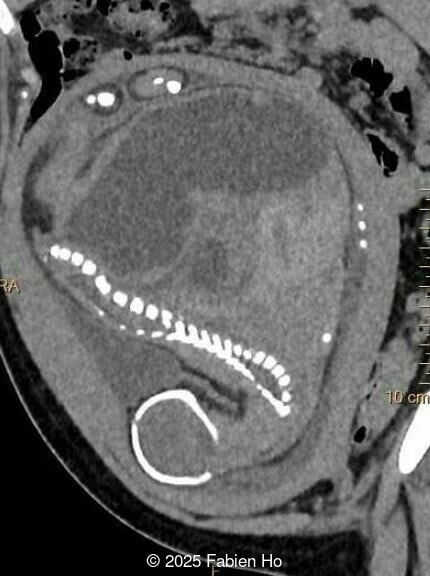

At 36 weeks gestation, the abdominal findings were unchanged however, the bones appeared short (<1st percentile) and the spine had an unusual appearance, therefore a computed tomography was performed at 37 weeks gestation.

Our prenatal ultrasound revealed a male fetus with megabladder, dilation of both ureter and kidneys, and thinned kidney parenchyma consistent with Lower Urinary Tract Obstruction (LUTO). Additional findings suspected on ultrasound and confirmed on computed tomography included:

- Dysostosis: Hemivertebrae L3, fused L4-L5, abnormal left foot with short metatarsals and missing phalanges

- Suspicion of dilated bowel in the left flank, in addition to dilated urinary tract